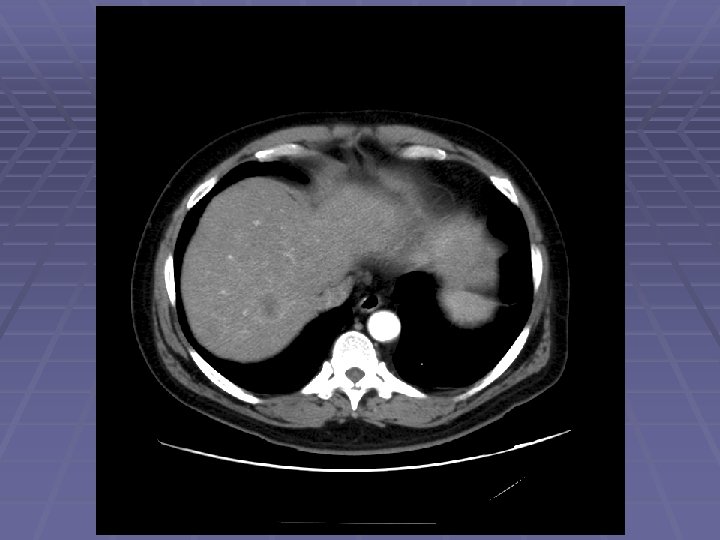

EUS Evaluation of Left Lobe of Liver